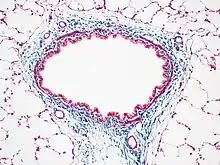

Masson's trichrome stain

Masson's trichrome is a three-colour staining procedure used in histology. The recipes evolved from Claude L. Pierre Masson's (1880–1959) original formulation have different specific applications, but all are suited for distinguishing cells from surrounding connective tissue.

Most recipes produce red keratin and muscle fibers, blue or green collagen and bone, light red or pink cytoplasm, and dark brown to black cell nuclei.

Another common variant is the Masson trichrome & Verhoeff stain, which combines the Masson trichrome stain and Verhoeff's stain.[2] This combination is useful for the examination of blood vessels; the Verhoeff stain highlights elastin (black) and allows one to easily differentiate small arteries (which typically have at least two elastic laminae) and veins (which have one elastic lamina).